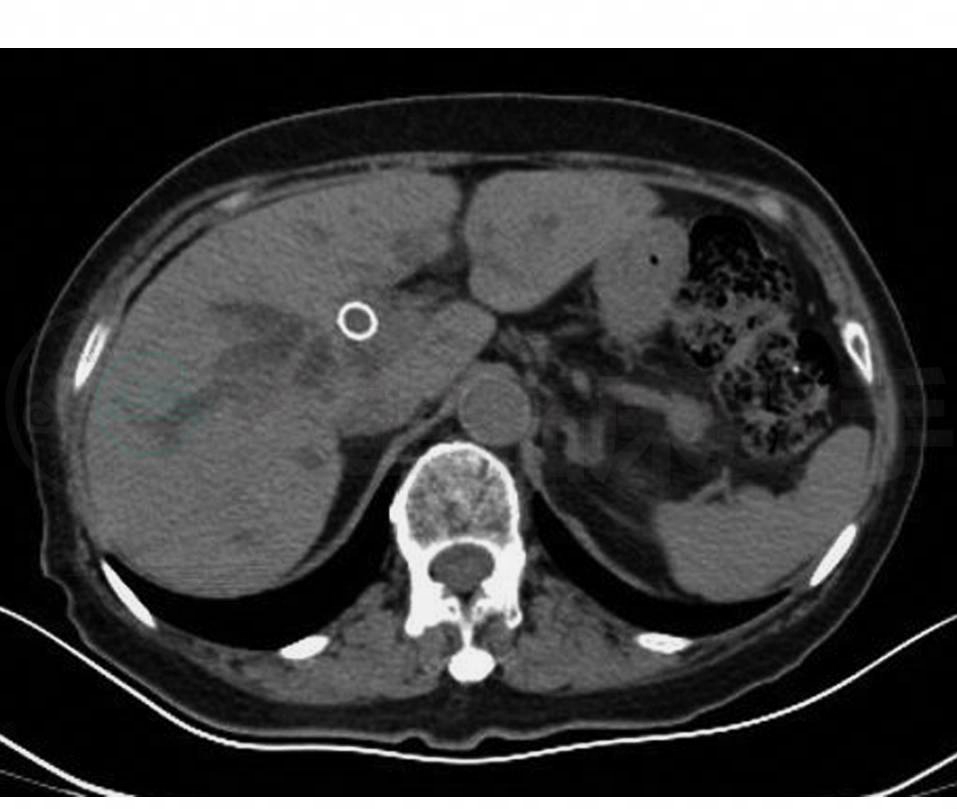

上腹CT平扫(图1):符合胆道支架置入术后改变;肝门部胆道梗阻,考虑胆管癌累及肝门胆管汇合部,胆囊管受累可能性大。

图1 上腹部CT

胆道支架置入术后,肝门部胆道梗阻